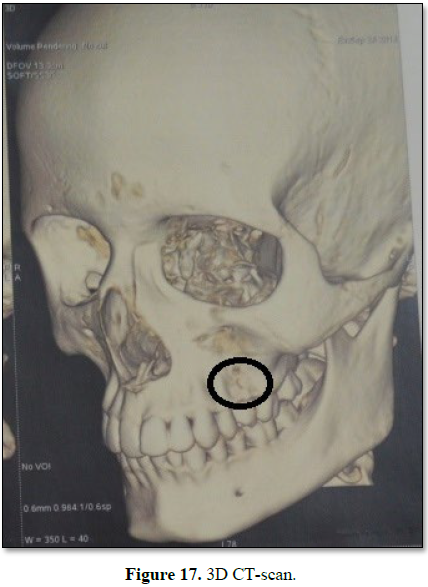

Thereafter 3D-CT scan was done for precise evaluation and assessment of

the lesion which showed bone destruction/perforation of cortical plate in that

region, representing its aggressive nature (Figure 3).

CT scan showed excessive bony thinning and destruction with resorption of

buccal cortical plates, showing signs of its aggressive nature.